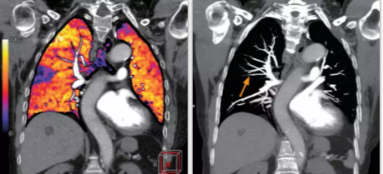

相比傳統(tǒng)成像方式,肺部柔性減影技術(shù)通過人工智能,對平掃數(shù)據(jù)和CT肺動脈血管掃描數(shù)據(jù)進行智能比對,解碼并識別各個器官(肺、氣管、肺動脈、肺靜脈、主動脈等)的空間位置,并在三維空間中進行體素級的柔性配準,從而極大提升了不同序列數(shù)據(jù)的空間位置的一致性。通過肺部柔性減影技術(shù)可得到肺強化碘圖,可以顯示出傳統(tǒng)CTPA圖像看不到的小栓塞病變,提高了栓塞檢出率,其結(jié)果甚至可與SPECT吻合。

肺智能柔性減影成像功能發(fā)現(xiàn)亞段肺栓塞

柔性成像功能為開拓者Ai-640CT的臨床應(yīng)用帶來了很多顛覆式的拓展功能,如佳能獨有的能譜+灌注的多模態(tài)成像方案。

此次,佳能對能譜成像方案也進行了升級,結(jié)合了AI的柔性能譜技術(shù)從能譜技術(shù)的四個基本判別條件——輻射劑量,數(shù)據(jù)精度,覆蓋寬度和能量分離度著手,分別優(yōu)化了以上四種技術(shù),實現(xiàn)了kV和mA的獨立切換。高低kV的切換保證了能量分離度;根據(jù)體位自動調(diào)整的mA有效降低了輻射劑量;16厘米容積探測器解決了覆蓋寬度的問題;單球管配合AI感知掃描技術(shù)與AI器官柔性配準算法,確保了數(shù)據(jù)精度。以此作為保障,佳能能譜+灌注的多模態(tài)成像方案僅需一次掃描即可同時獲得能譜數(shù)據(jù)和灌注數(shù)據(jù)。